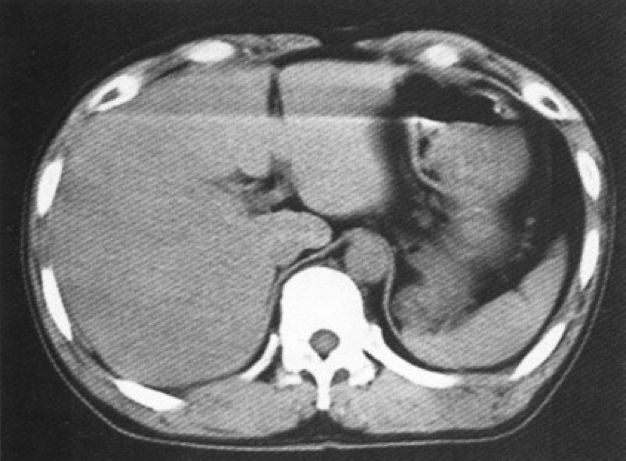

病人引起的伪影

扫描部位的移动导致伪影称之为运动伪影,它是伪影的主要来源。 消除办法:在进行CT扫描前应做好病人呼吸的训练工作,另外还应采用短时间的扫描程序进行CT扫描。

(运动伪影)